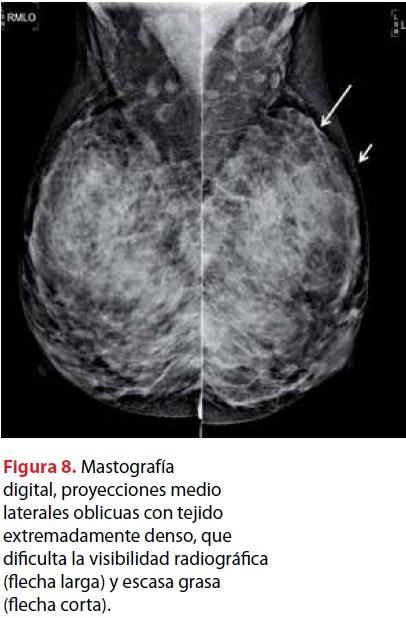

Integracion De La Imagen En La Patologia Mamaria Gaceta Mexicana De Oncologia